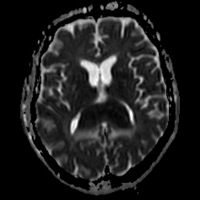

Noncontrast CT of the head demonstrates a relatively hyperdense, expansile mass within the splenium of the corpus callosum. A mild rim of hypodensity surrounds the margins of the mass, extending into the parieto-occipital white matter (WM). T1-weighted image (T1WI) reveals a mass that is isointense to gray matter (GM) and isointense to mildly hyperintense on T2WI. The fluid-attenuated inversion recovery (FLAIR) sequence confirm the presence of a hyperintense, expansile mass infiltrating the splenium, with only minimal contiguous hyperintensity within the WM, presumably vasogenic edema. Furthermore, T2WI and FLAIR sequences confirms the presence of internal cystic degeneration. Postcontrast T1WI reveals a strongly enhancing, partially necrotic mass. Abnormal restricted diffusion verified by the trace images and corresponding apparent diffusion coefficient (ADC) map.

| Figure 3 — Mass is iso- to mildly hyperintense to GM on T2WI, with internal foci of cystic degeneration/necrosis. | Figure 4 — FLAIR sequence shows hyperintense lesion with areas of internal cystic degeneration/necrosis and mid surrounding vasogenic edema. |